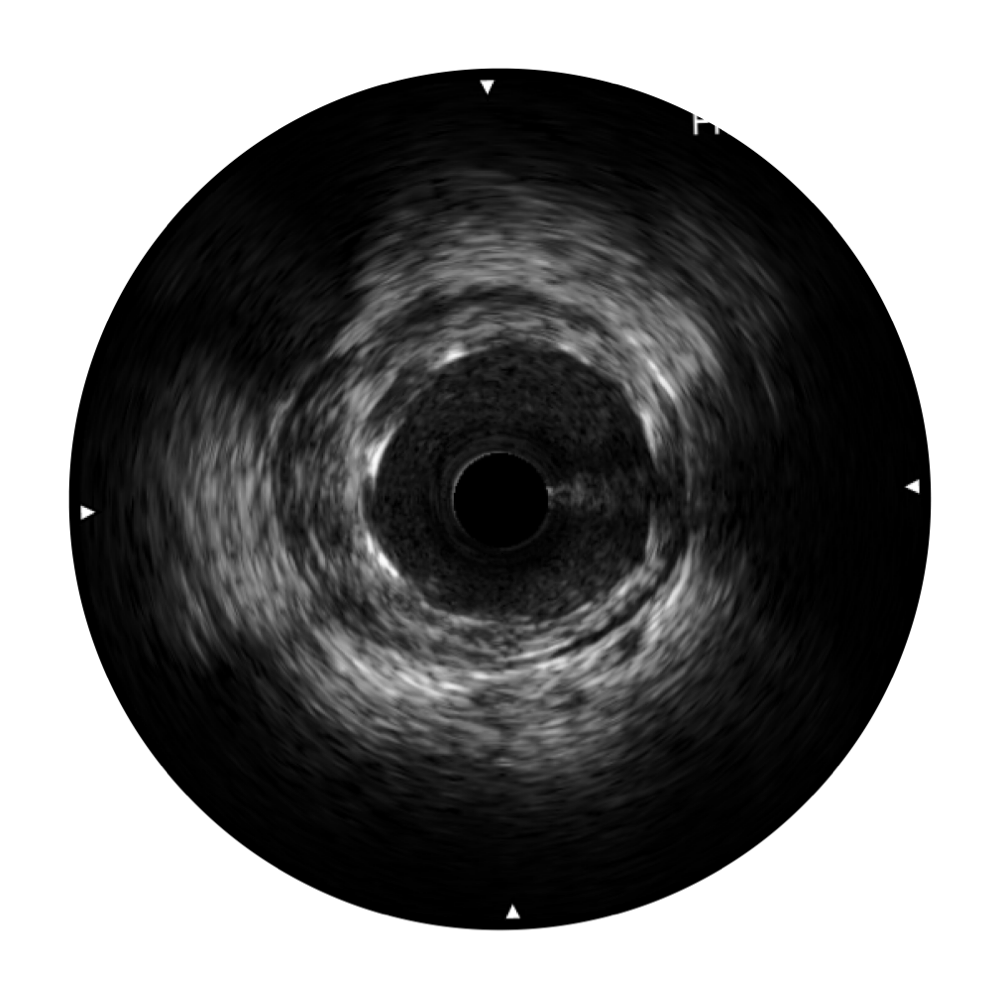

传统IVUS图像

对比传统IVUS导管成像,1xBET宽频IVUS图像的近场支架梁显影更细腻,远场中膜外血管仍清晰可辨,兼顾远中近,兼顾分辨力与穿透深度